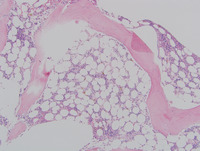

Bone Marrow

The bone marrow shows a hypocellular

marrow for age with atypical megakaryocytes and no increase in blasts. Cytogenetic analysis of the marrow showed an abnormal karyotype involving  monosomy 7.  DNA sequencing revealed a germline mutation in GATA2. Diagnosis:  Refractory cytopenia of childhood, GATA2 deficiency related.

Core Biopsy

Core biopsy showing megakaryocytic atypia with hypolobated forms and a form with separated nuclei.